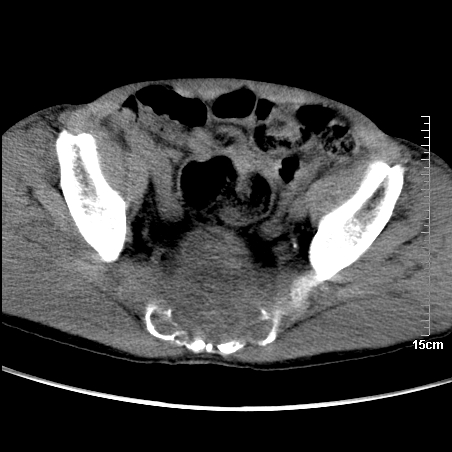

标题: CT16886:骶尾部占位:1.脊索瘤?2.巨细胞瘤?

增强:

1、骶尾部巨大软组织肿块,部分骶尾骨以被软组织肿块代替,呈不规则侵蚀;病变突向盆腔内;增强扫描病变呈不均质强化;首先考虑脊索瘤。不支持的一点就是病变内无钙化。

2、发生于骶尾椎者须与骨巨细胞瘤鉴别,骨巨细胞瘤一般发在上疗骶椎,肿瘤内无钙化,一般无侵袭性生长的表现。